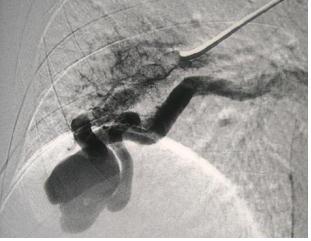

外伤后出血的栓塞

外伤后可见造影剂外溢 |

微导管选择至出血血管 |

出血血管的微弹簧栓子栓塞 |

栓塞后造影 |